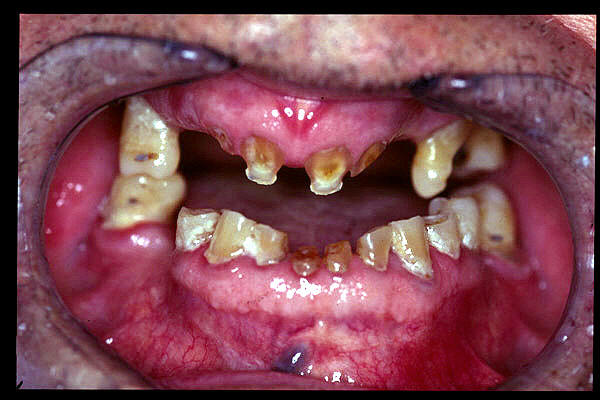

CM Edentulismo parcial, restos radiculares, caries y placa bacteriana